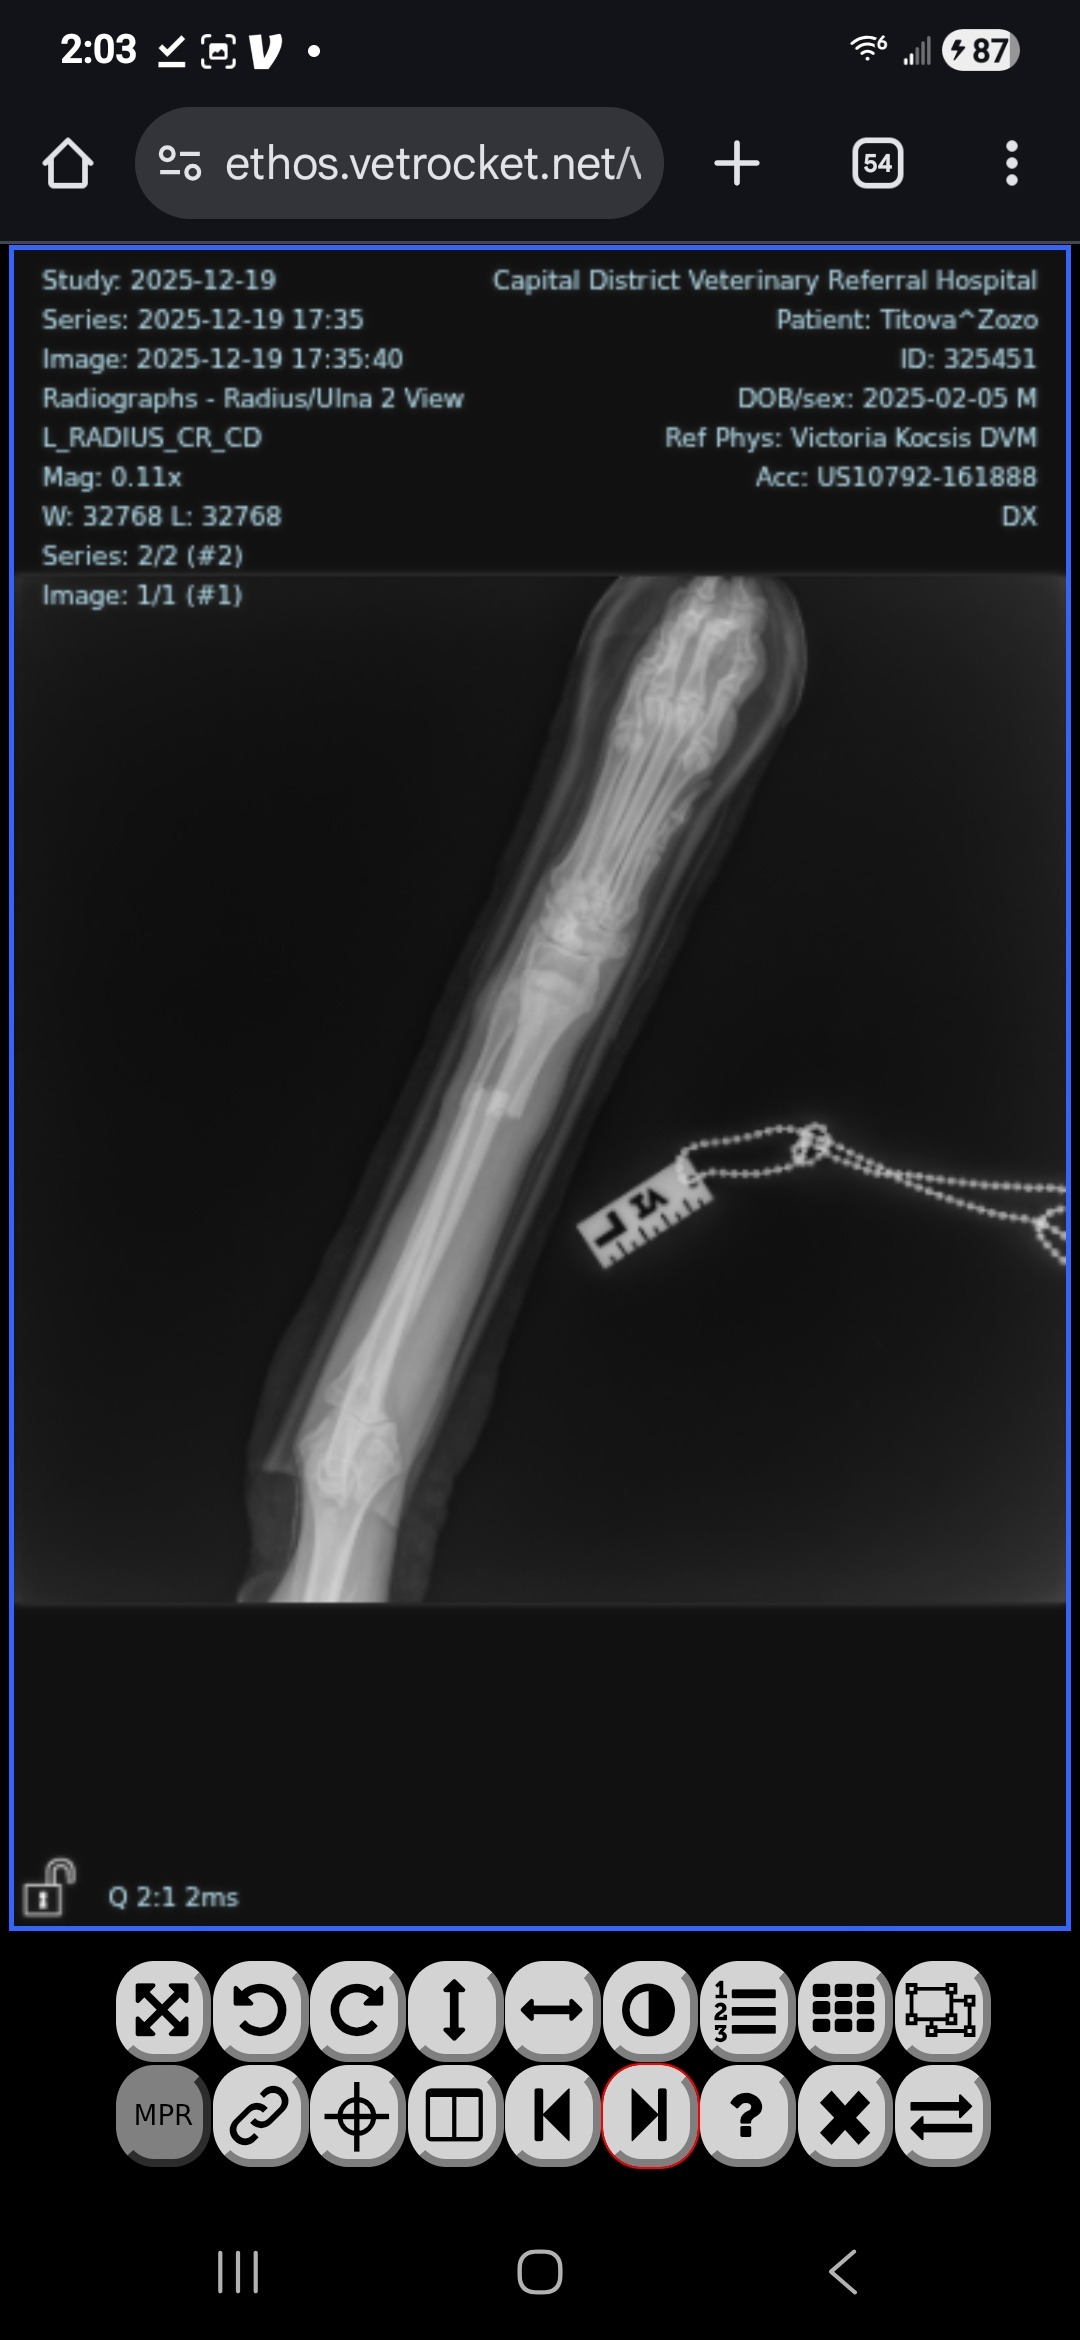

On Thursday overnight, my world turned upside down. Zozo, my 10-month-old Belgian Sheepdog and service dog in training, landed poorly while jumping and broke both bones in his front left leg. He’s just a baby — full of life, curiosity, and joy — and suddenly he’s facing an injury that could permanently change his future.

Right now, Zozo is undergoing weekly sedated re-splints to stabilize his leg. His veterinary team believes he is a strong candidate for surgery, with an excellent chance at healing and living a full, active life — but the surgery must be done within the next 2 weeks to save his leg. The cost of surgery and care is more than I can manage on my own.